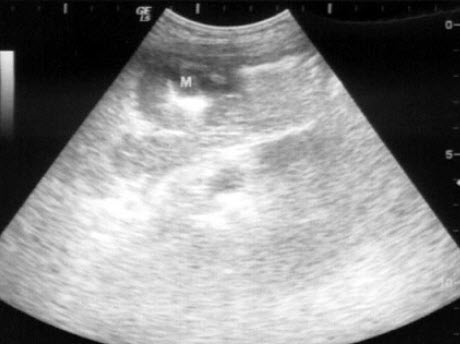

男,49岁,上腹不适1个月余。结合超声声像图,诊断为()

A.肝血管瘤

B.肝癌

C.局限性脂肪肝

D.肝脓肿

E.肝囊肿